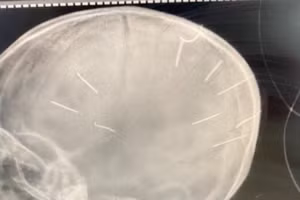

Vụ cháu bé 3 tuổi có nhiều đinh ở đầu: Công an lấy lời khai của nhiều người

GD&TĐ - Công an huyện Thạch Thất (Hà Nội) đã tiến hành lấy lời khai với mẹ cháu bé 3 tuổi nghi bị bạo hành và những người liên quan để phục vụ công tác điều tra làm rõ vụ việc.